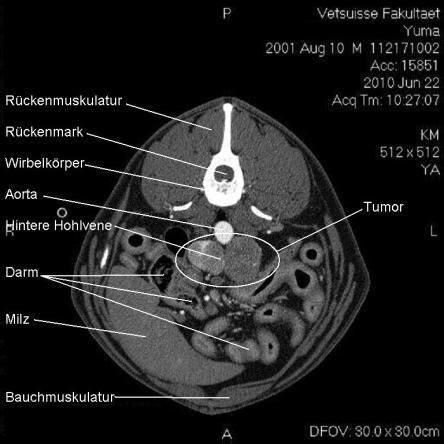

Die Computertomographie (CT) liefert mittels eines röntgenähnlichen Verfahrens ein dreidimensionales Bild des untersuchten Körperteils. Da das untersuchte Tier vollständig ruhig liegen muss, wird Yuma zur Untersuchung narkotisiert.

Im CT wird ersichtlich, dass sich der Tumor, welcher von der linken Nebenniere ausgeht, schon sehr weit in das Gefässystem von Yuma vorgearbeitet hat. Krebsausläufer finden sich wie erwartet in der Hohlvene, aber auch in der Nierenvene sowie in einer weiteren grossen Vene. Der Geschwulst ist somit inoperabel.